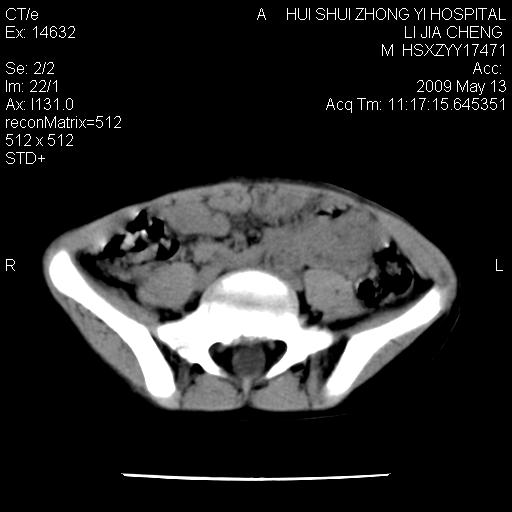

标题: PED1887:男性,6岁。反复脐周疼痛2年余。请各位老师看下腹 [打印本页]

标题: PED1887:男性,6岁。反复脐周疼痛2年余。请各位老师看下腹

该患者可自行好转,大小便未见异常,化验:便未见虫卵,血常规:wbc:8000;淋巴3600,中性45%

肠道准备不足,im15---------------------18左侧腹腔病变?